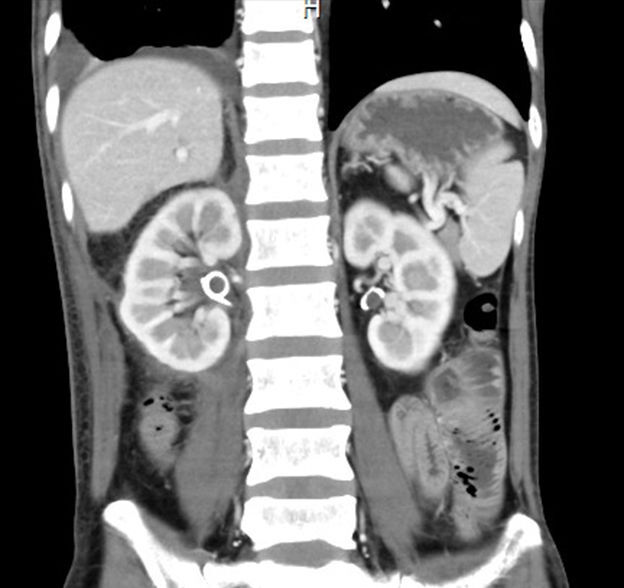

林先生今年4月份起逐渐感觉右侧腹部点闷胀,躺着的时候目测右边肚子比左边的肚子稍高。在粤东当地医院做了腹部CT,竟然发现肚子里长了一个大肿物。当地医院推荐到广州的大医院作进一步检查治疗。在广州,林先生做了PET-CT,发现肿物已长到12.88×11.48×17.15厘米大小,进一步检查了病理,诊断为去分化脂肪肉瘤。

▲4月份CT检查发现巨大肿物,右肾受挤压

去分化脂肪肉瘤是一种高度恶性的肿瘤,手术是主要治疗手段。但是林先生的情况非常特殊,他体内的肿物呈马蹄形,累及了周边多个组织器官,包绕了重要血管,而且肿瘤周边血供非常丰富,稍有不慎很可能危及生命。